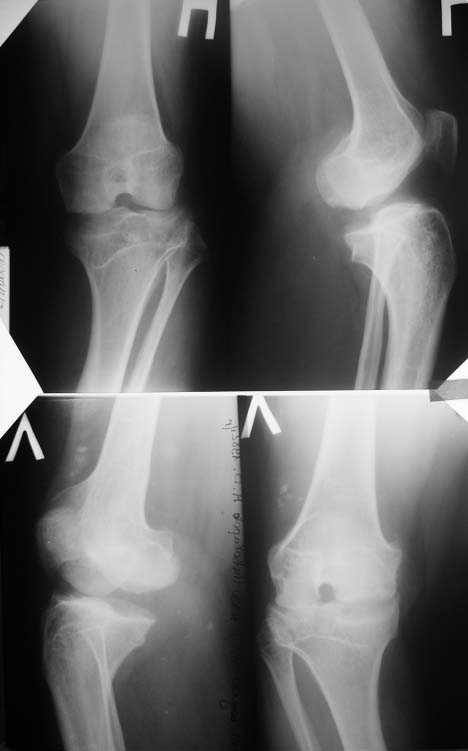

Прямая и боковая обоих коленных суставов

Алексей, судя по снимкам, правый тазобедренный сустав нуждается в замене. Думаю, что получится поставить протез без дополнительных конструкций во впадину и особых ножек. Важным является диаметр канала. Надо по шаблонам оценить размер. Самые маленькие из известных мне ножек в России предсталены у De Puy (бесцементная 6), и новинка от BIOMET бесцементная диспластическая ножка.

О коленях надо больше клинической информации, а главное чего хочет сам пациент.